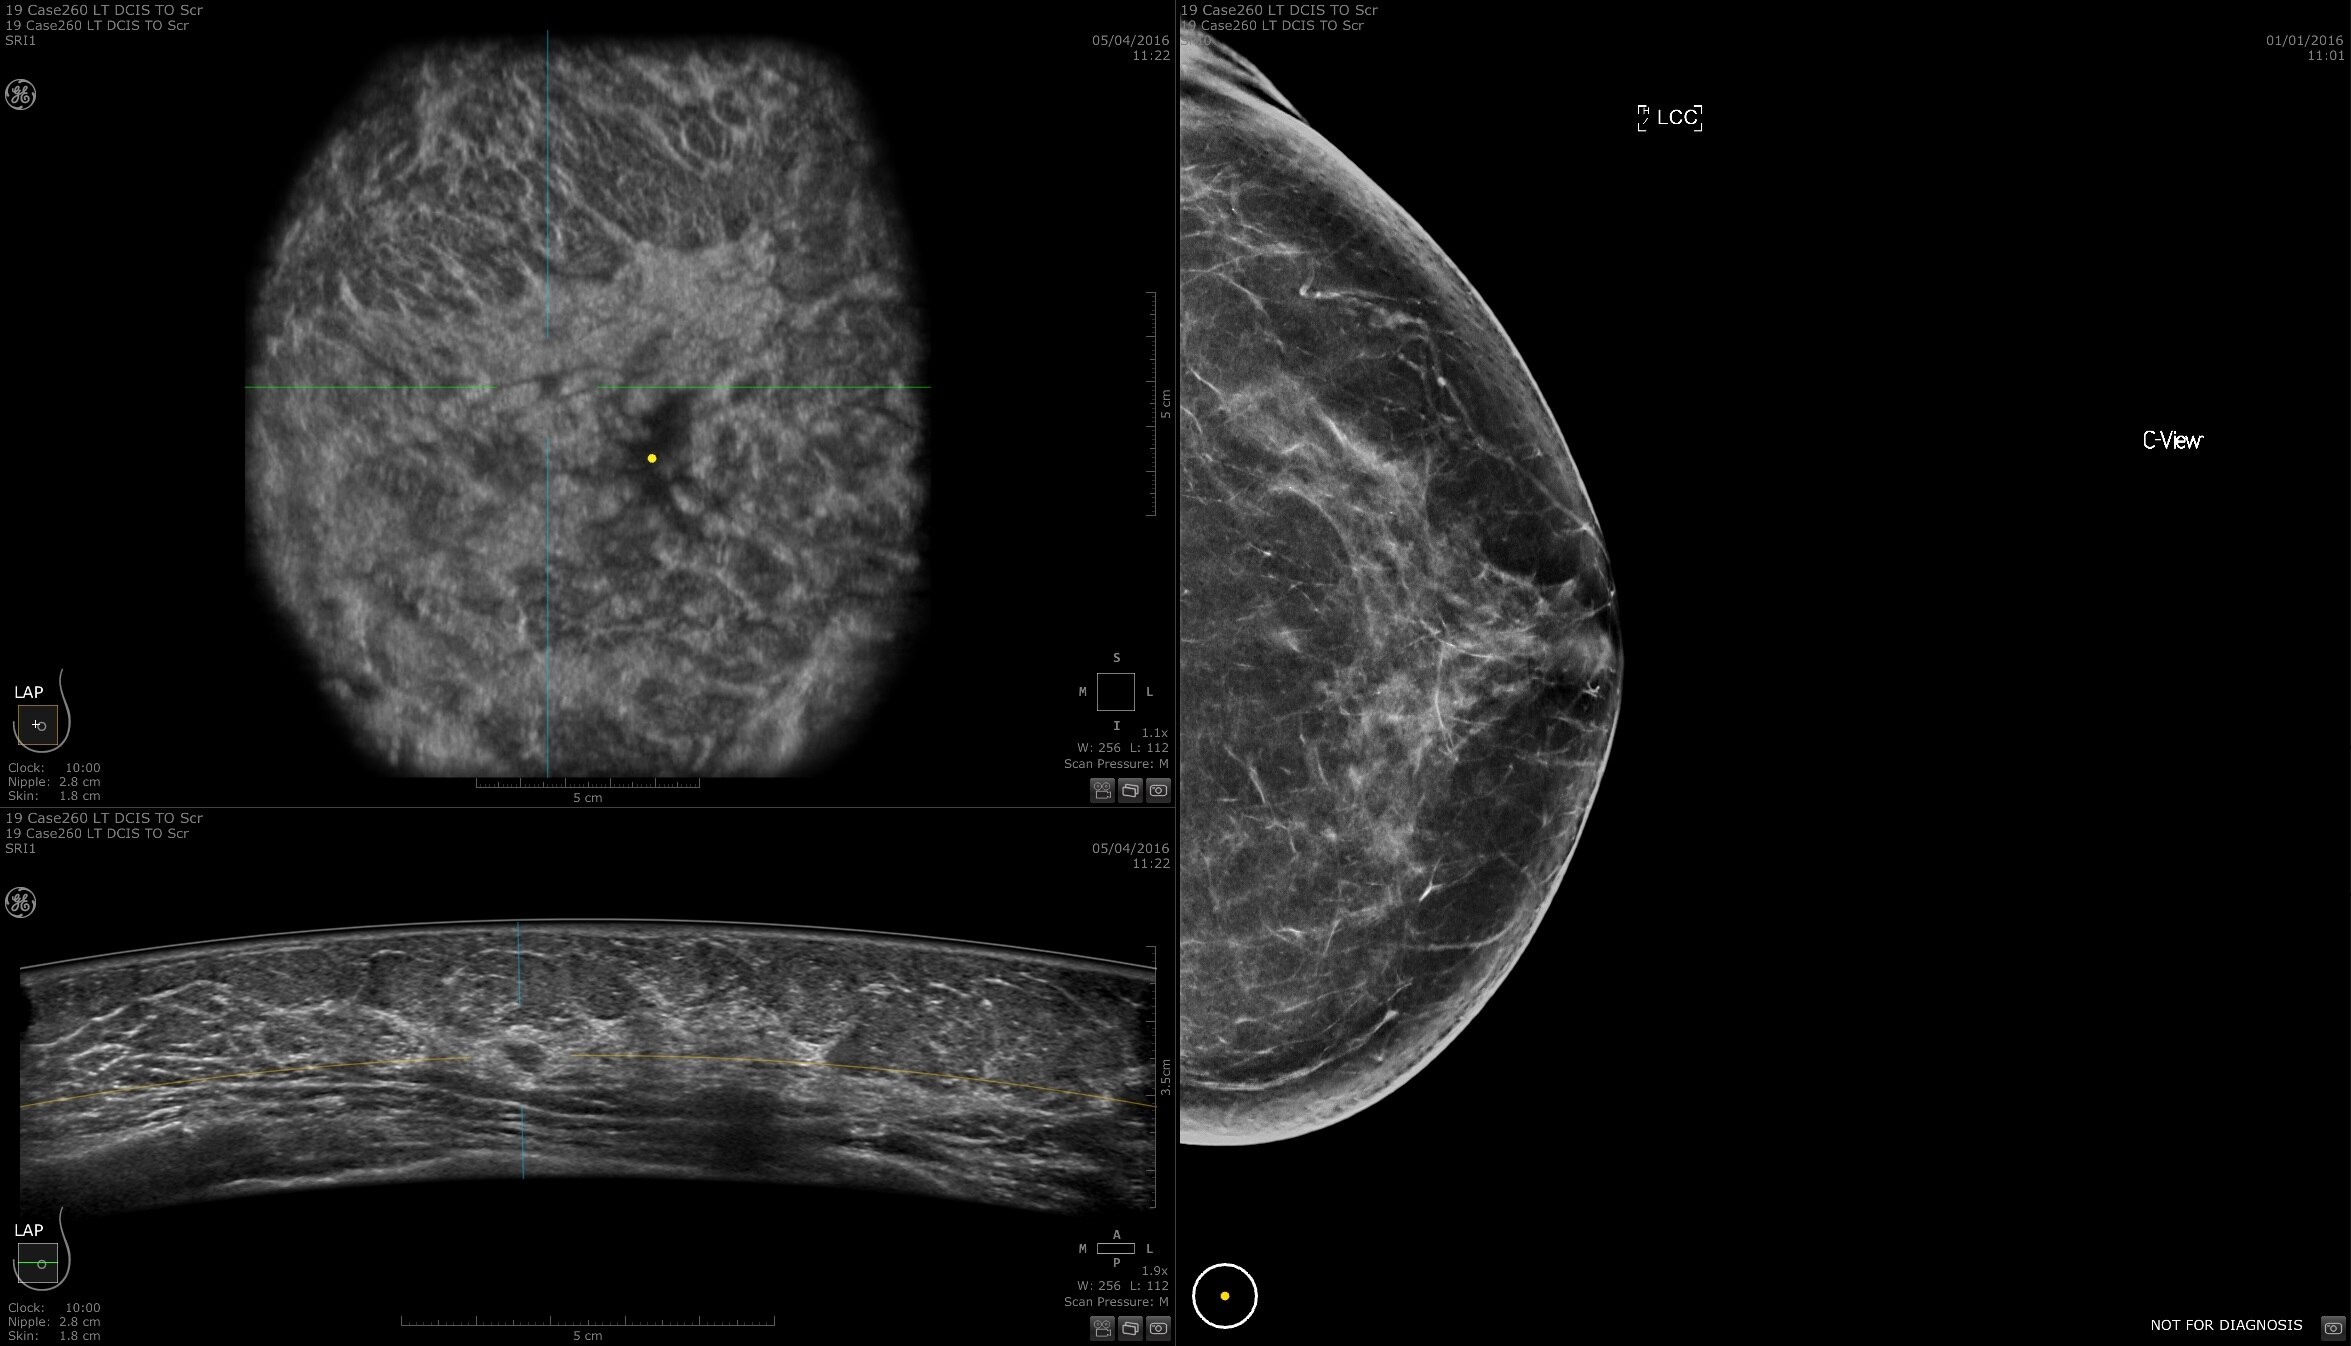

FOLLOW UP

Easy monitoring of treatment progress

Invenia ABUS 2.0 uses patient friendly imaging to help monitor treatment progress with the goal of avoiding complications and risk of cancer recurrence. Features such as auto prior function provide a standardized comparison with previous findings.